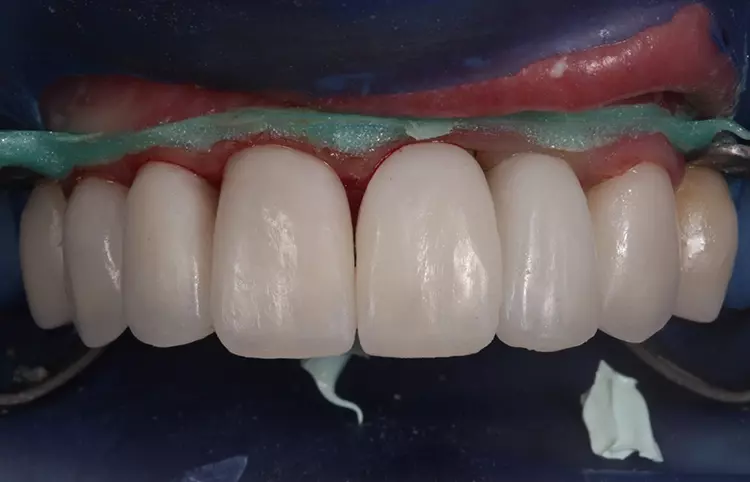

Im Oberkiefer fand die abschließende Präparation (nach Hart- und Weichgewebeaugmentation regio 22 und temporärer Versorgung mit LZP für 12 Monate) für die definitive Versorgung der Front 13 bis 23 mit Vollkeramikrestaurationen (Presskeramikgerüste „Creapress“, KLEMA, vollverblendet mit Feldspatkeramik Creation CC, KLEMA) statt (Abb. 13 und 14). In den Folgesitzungen schlossen sich die Abdrucknahme, Zentrikbissnahme, Gesichtsbogenübertragung, Anproben und definitive Eingliederung an.